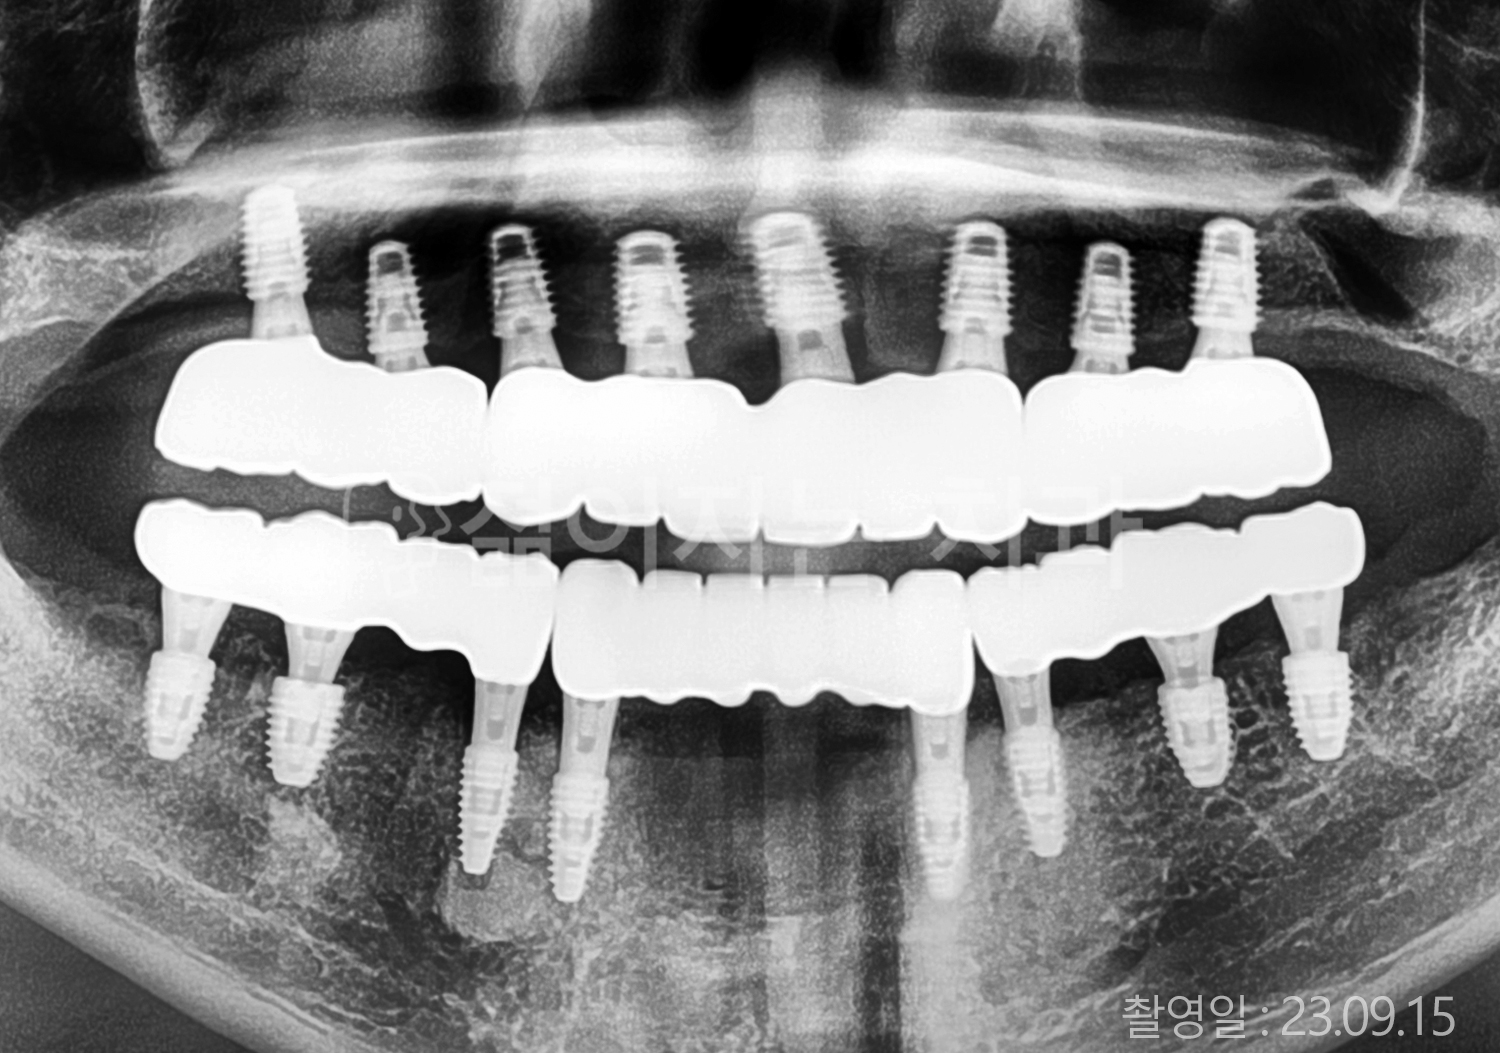

• 80대 전체치아 10개 이상 임플란트

• 60대 고혈압, 당뇨, 고지혈증 전체치아 10개 이상 임플란트

• 60대 전체치아 10개 이상 임플란트

• 60대 고혈압, 고지혈증 전체치아 10개 이상 임플란트

• 50대 고혈압, 당뇨, 고지혈증 전체치아 10개 이상 임플란트

• 70대 골다골증, 파킨스병 전체치아 10개 이상 임플란트

• 40대 전체치아 10개 이상 임플란트

• 60대 골다골증 전체치아 10개 이상 임플란트

• 40대 고혈압 전체치아 10개 이상 임플란트

• 50대 전체치아 10개 이상 임플란트

• 70대 전체치아 10개 이상 임플란트